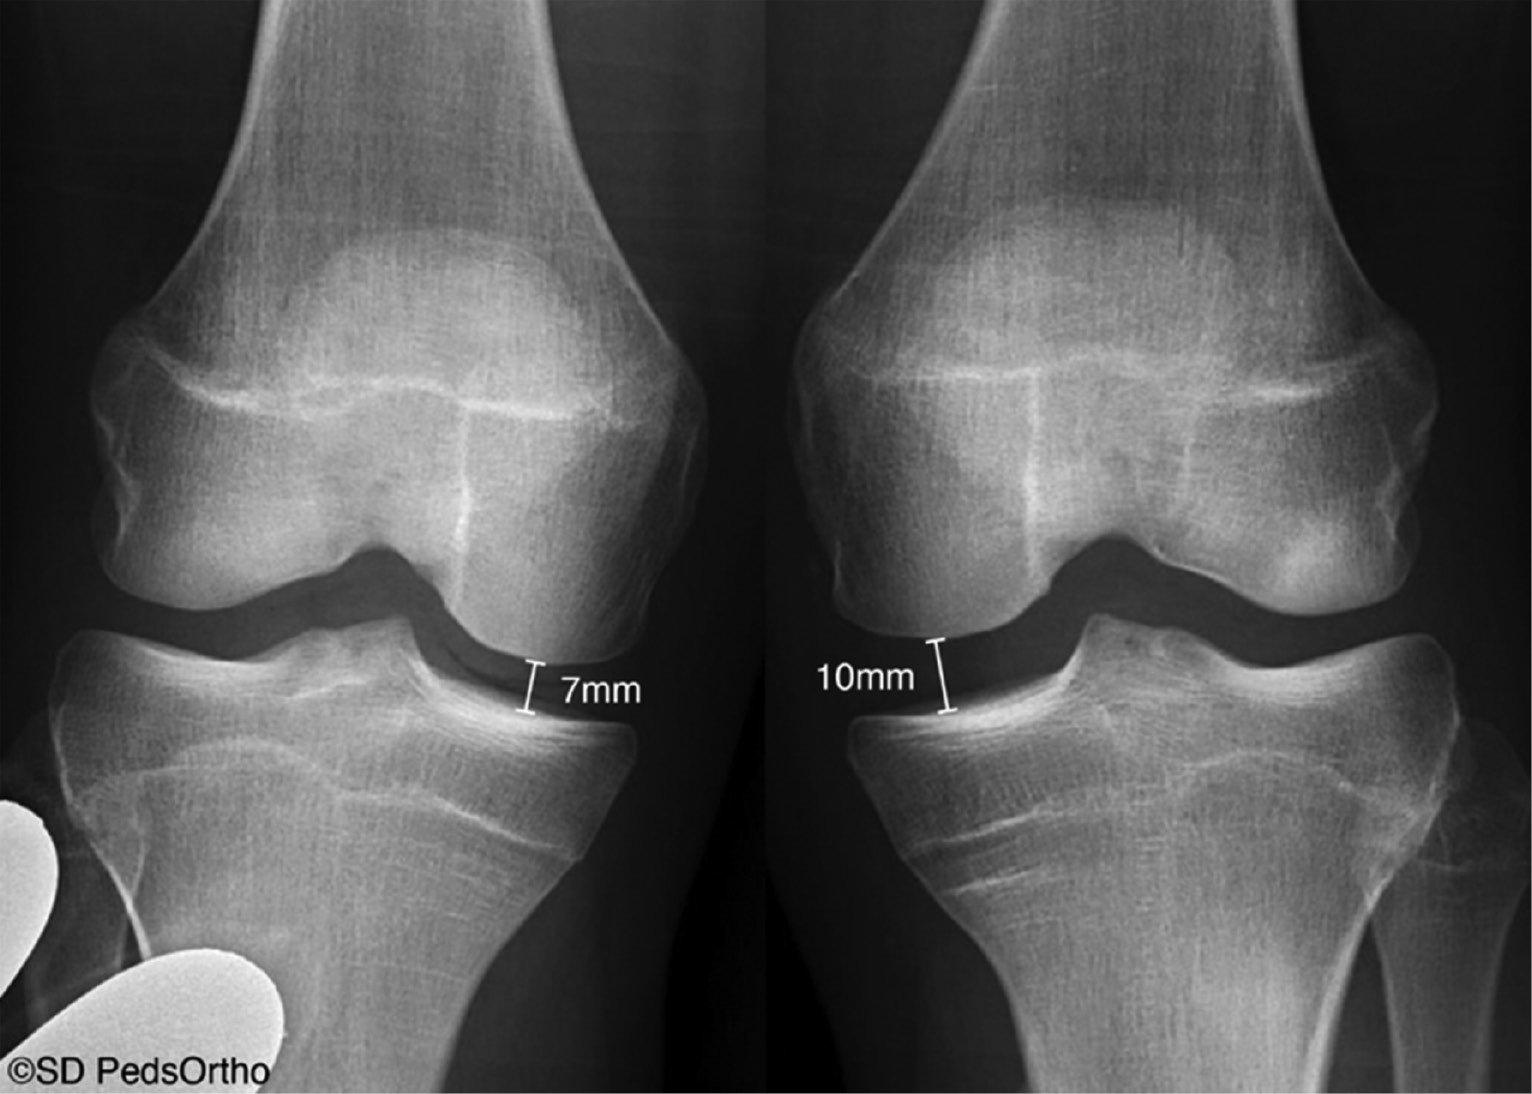

Stress Radiographs

Stress radiographs have become increasingly important in the workup and management of medial-sided knee injuries. These radiographs help objectively assess the extent of the medial-sided injury. While established thresholds exist in the adult population, these have not been validated in pediatric patients. Stress radiographs are performed with the practitioner applying a valgus stress to the extremity with the patella pointed towards the ceiling and the knee flexed 15-30 degrees (Figure 6). The uninjured contralateral extremity is also imaged and serves as a comparison. It is usually more successful to begin imaging the uninjured extremity to decrease anxiety associated with obtaining these stress images on the injured leg. Additionally, timing the stress maneuver with the radiographer minimizes the amount of time stress is held. Most patients tolerate these stress views without significant discomfort. The gapping between the medial femoral condyle and the medial tibial plateau is measured and compared to the uninjured extremity (Figure 7).

Figure 7. Valgus stress radiographs of a patient with a complete tear of the superficial MCL seen with a 3 mm side-to-side difference between the left and right knees.